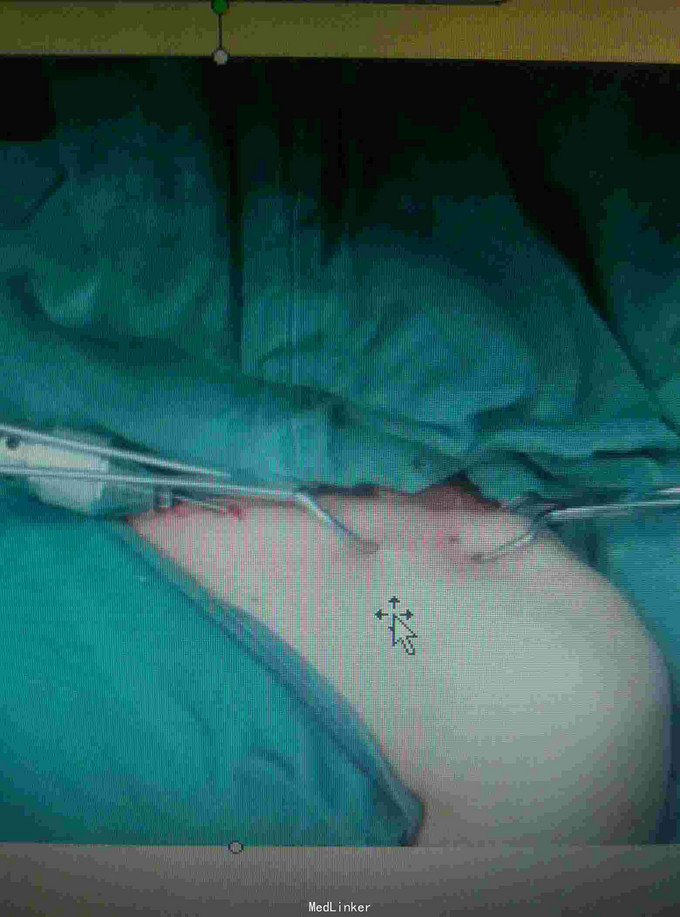

患者,53岁,男性,摔伤致左肩部疼痛,活动受限2小时入院

查体:左锁骨处压痛,畸形,活动受限,入院完善影像学检查明确诊断 ,排除肺部,神经血管损伤。

诊断:左锁骨骨折, 治疗:闭合复位TEN固定术